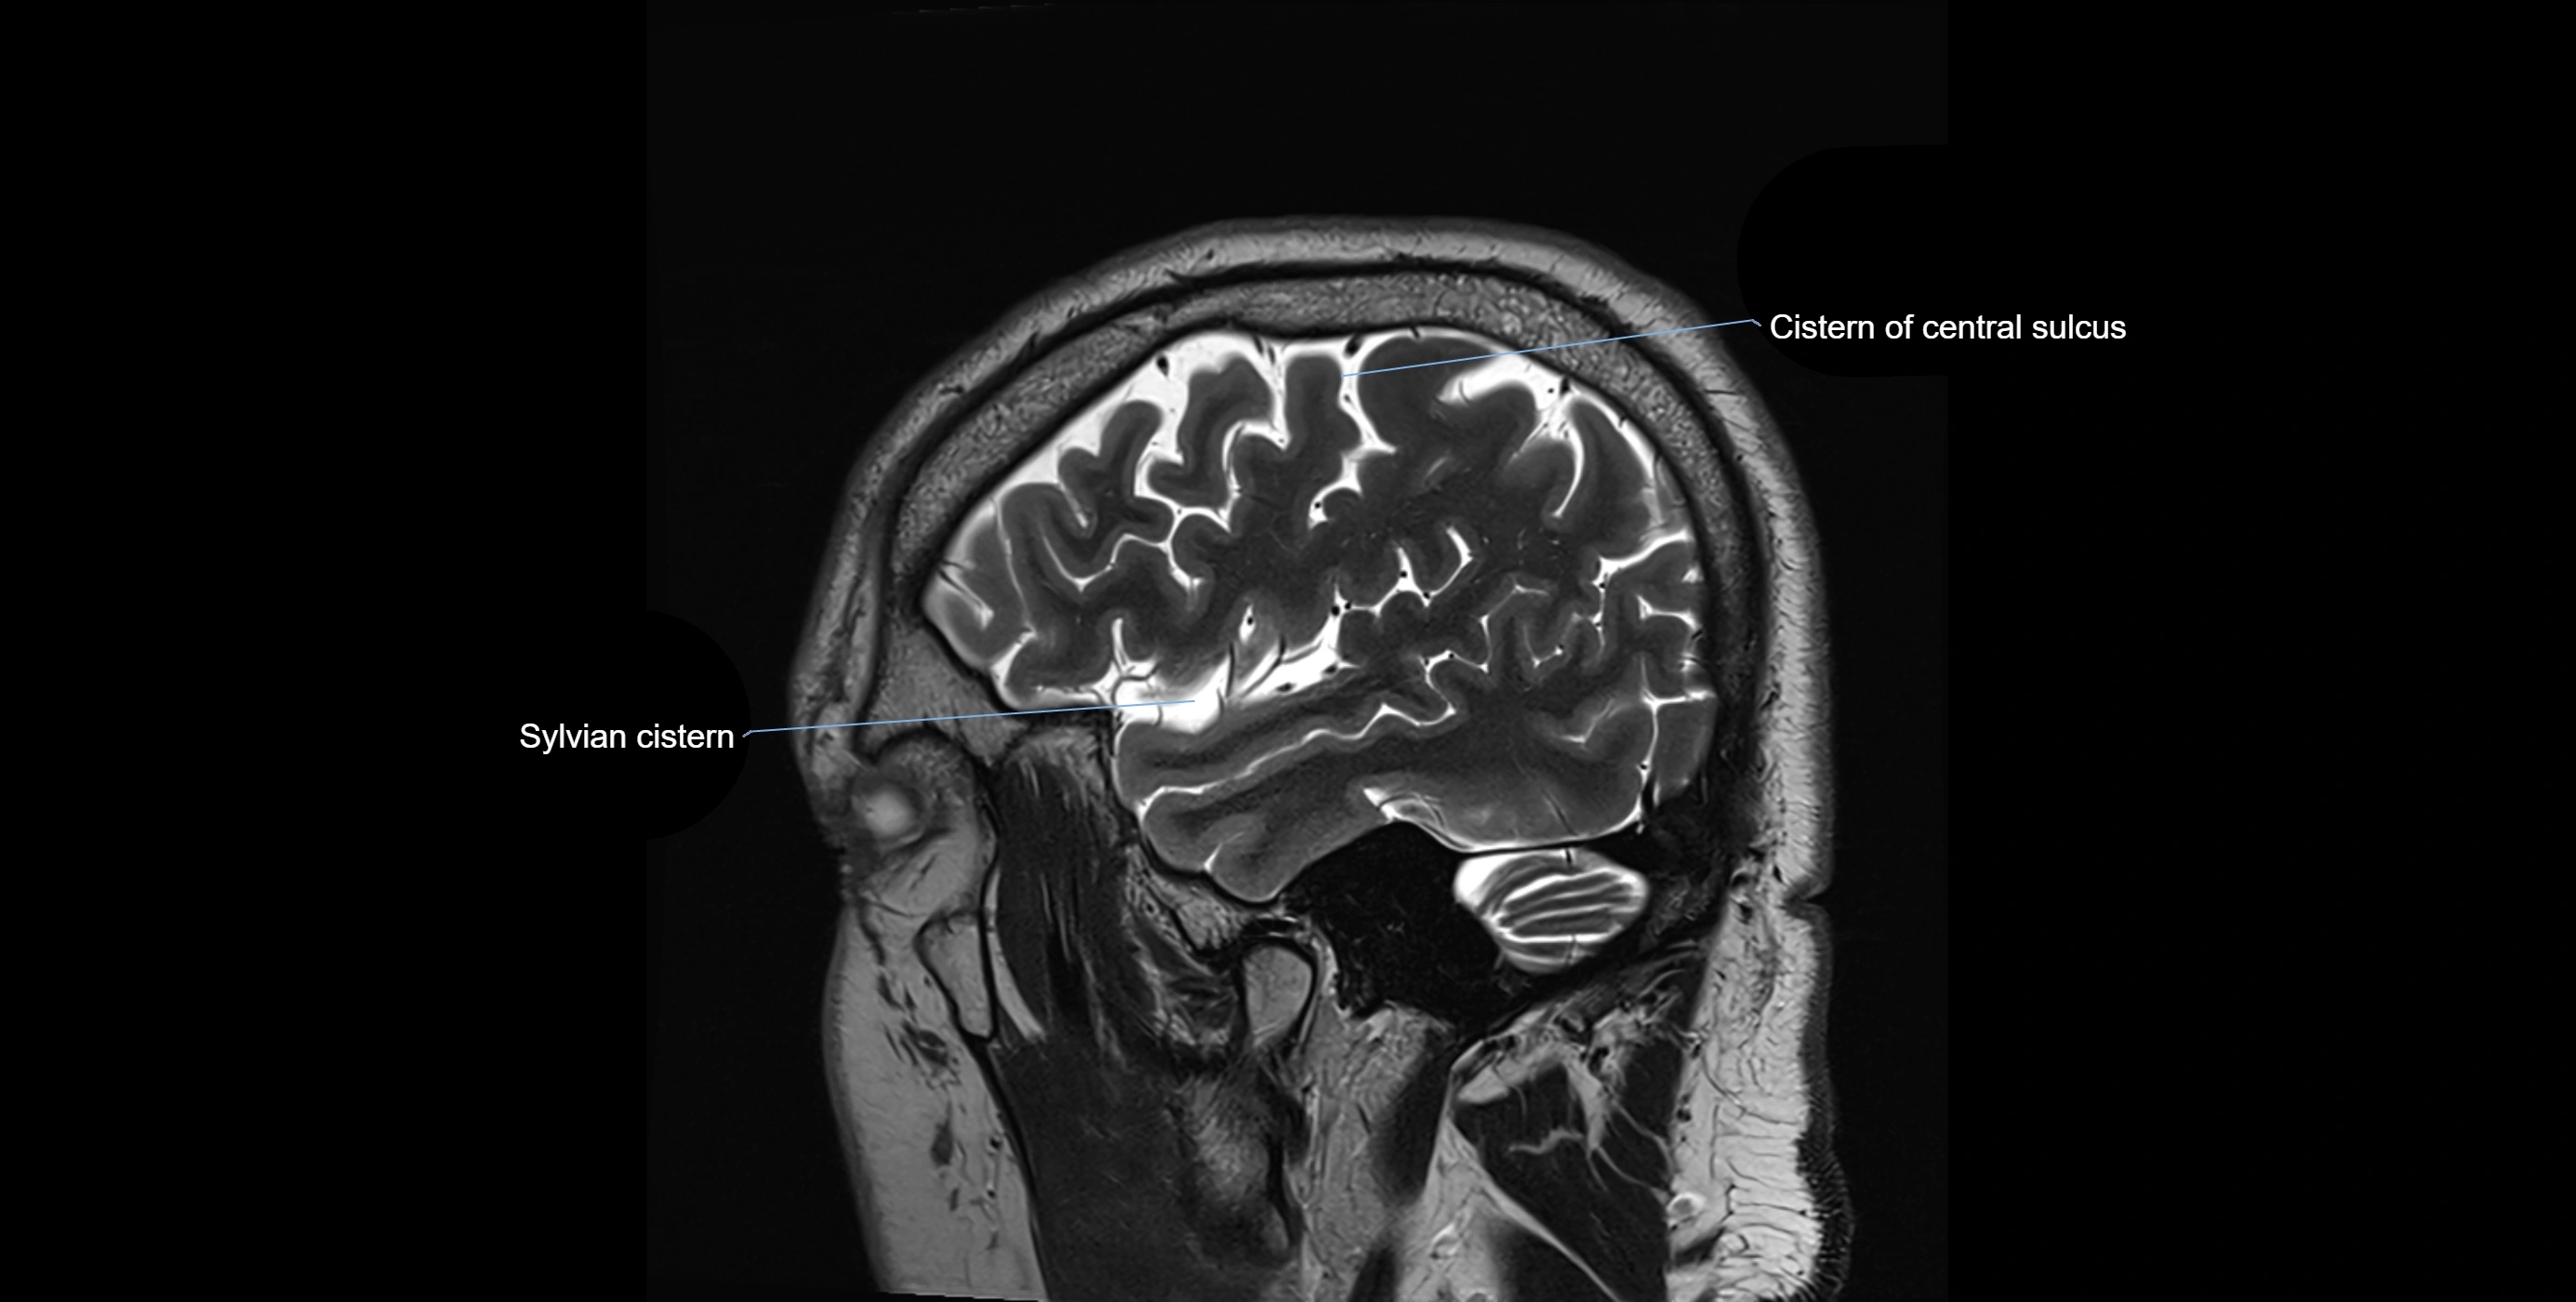

CT image

image